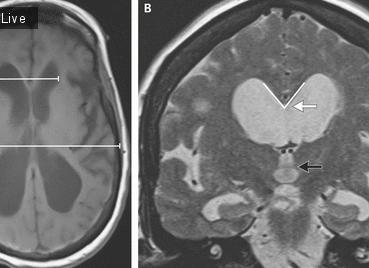

Фиг.1 Ребенку М. 6 месяцев выполнено вентрикулоперитонеальное шунтирование по поводу прогрессирующей внутренней гидроцефалии. До операции при КТ определена тяжелая степень гидроцефалии (ЛКИ = 51,5%).

Фиг.2 Спустя 6 месяцев после шунтирующей операции при контрольной КТ диагностирован полный регресс проявлений гидроцефалии, нормализация внутричерепных взаимоотношений (ЛКИ = 3,5%).

Фиг.3 Демонстрирует симметричное расширение ликворной системы. Отмечена корреляция между данными нейросонографии и КТ-морфометрии, соответствующими гидроцефалии легкой степени (ЛКИ = 7,6%).

Фиг.4 Демонстрирует деформацию и асимметрию ликворной системы после вентрикуло-перитонеального шунтирования гидроцефалии. По данным НСГ индекс Эванса = 0,47, что соответствует гидроцефалии легкой степени. Однако КТ морфометрия позволяет оценить вентрикуломегалию как более значимую (ЛКИ = 19,9%) — гидроцефалию средней степени.

Фиг.5 Демонстрирует грубый порок развития головного мозга, порэнцефалическую гидроцефалию с грубым поражением затылочных долей, однако передние отделы мозга изменены в меньшей степени. Индекс Эванса, измеренный по стандартной методике, равен 0,5, что соответствует легкой степени гидроцефалии. КТ-морфометрические измерения (ЛКИ = 43,5%) демонстрируют гидроцефалию тяжелой степени.